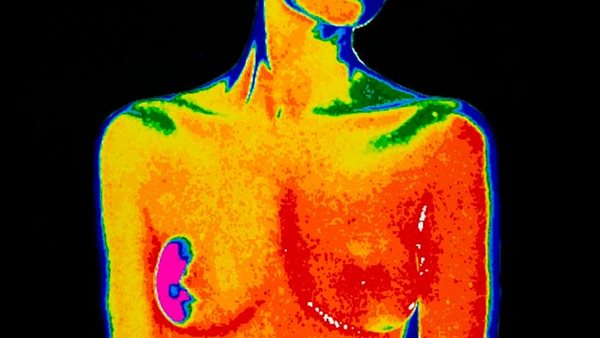

تغيير جذري.. نظام جديد لفحص سرطان الثدي يكشف أورام أخرى

وتم إطلاق نظام جديد لتصوير الثدي بالأشعة السينية واختبارات الجينات والفحوصات، ومن خلاله يمكن أن يُكتشف المزيد من السرطانات، ويجنب النساء ضائقة الإنذار الكاذب، في محاولة لمعالجة المخاوف طويلة الأمد من أن النظام عرضة للإنذارات الكاذبة.